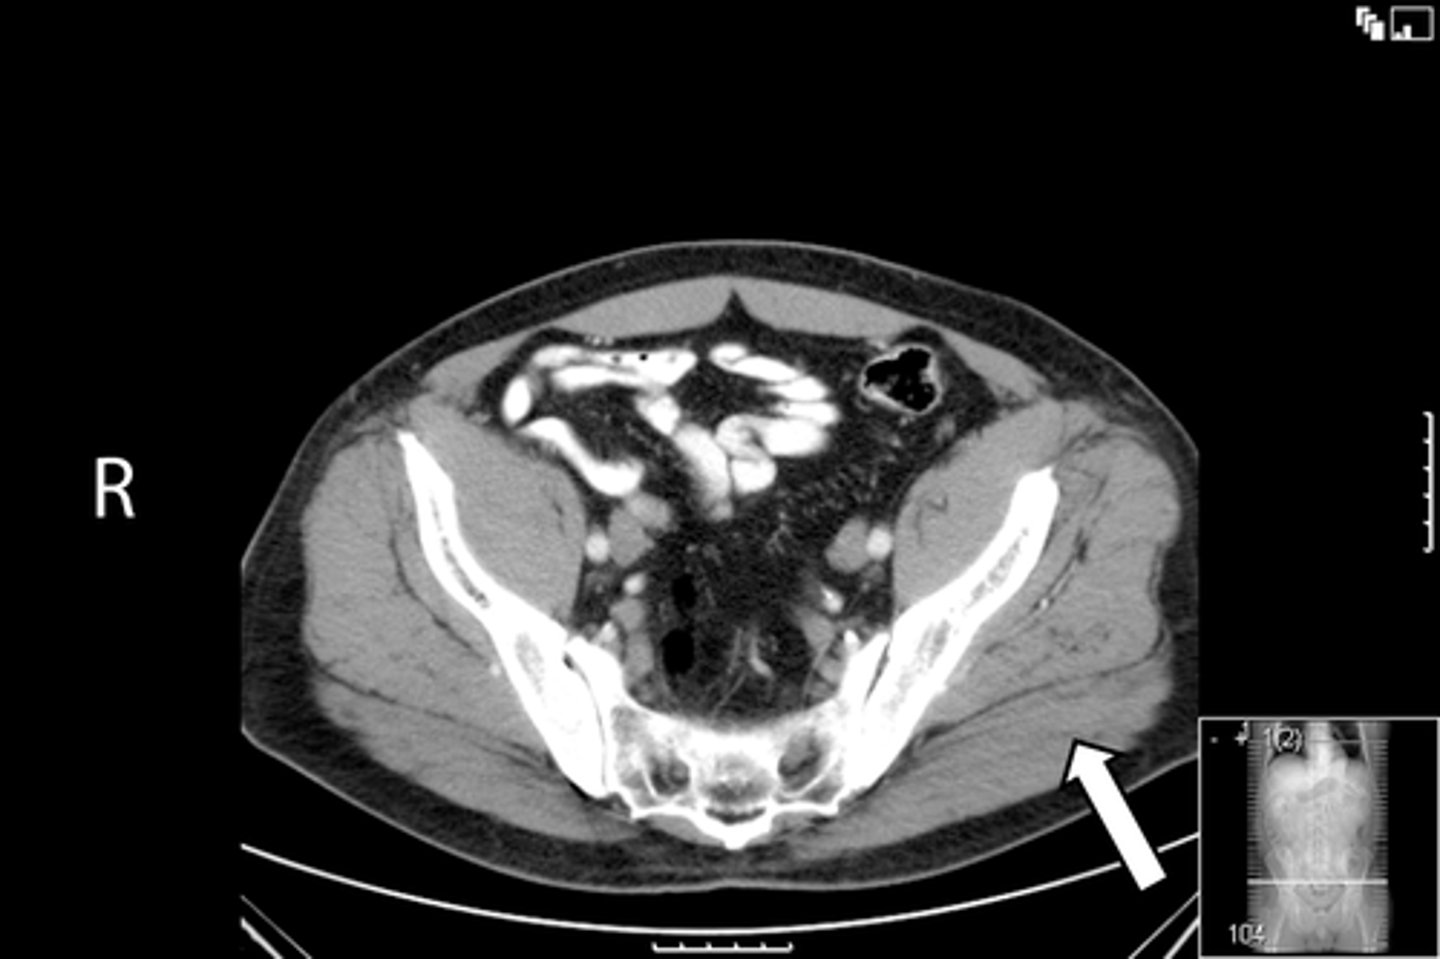

Axial bony pelvis CT

What is the image?

L acetabulum

What is indicated in the image?

L femoral head

L piriformis muscle

R femoral head

R piriformis muscle

R acetabulum (posterior part)

Sacrum